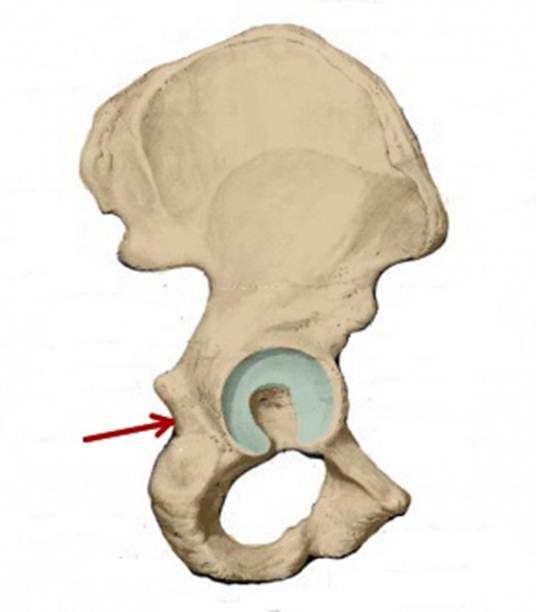

S: Стрелка указывает на tuber ischiadicum (латинский язык).

S: Стрелка указывает на foramen obturatum (латинский язык).

S: Стрелка указывает на tuberculum pubicum

S: Стрелка указывает на incisura ischiadica minor

S: Стрелка указывает на incisura ischiadica major

S: Стрелка указывает на incisura acetabuli

S: Стрелка указывает на sulcus obturatorius (латинский язык).